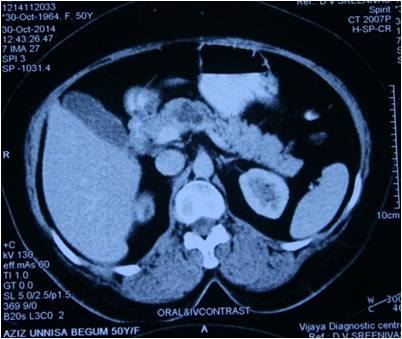

Interesting Images March 2019 : Patient came with an early stage carcinoma rectum, underwent Hemicolectomy surgery then lost to follow-up. Later after 9 month patients presented to us with Stage 4 disease (Carcinoma colon with Liver secondaries). Then we started her on treatment with Chemotherapy along with Monoclonal antibodies with six cycle of above said treatment patient achieved near complete remission. We could achieve very good results with chemotherapy even in patients with Stage 4 disease (Carcinoma colon with Liver secondaries).